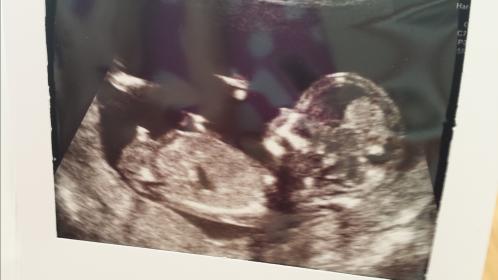

Attachment 21083

Boy

Boy!!

Baby Boy!

You weren't kidding...pretty obvious boy nub :) Congrats!

I'm going with strong boy.

Looks like boy nub